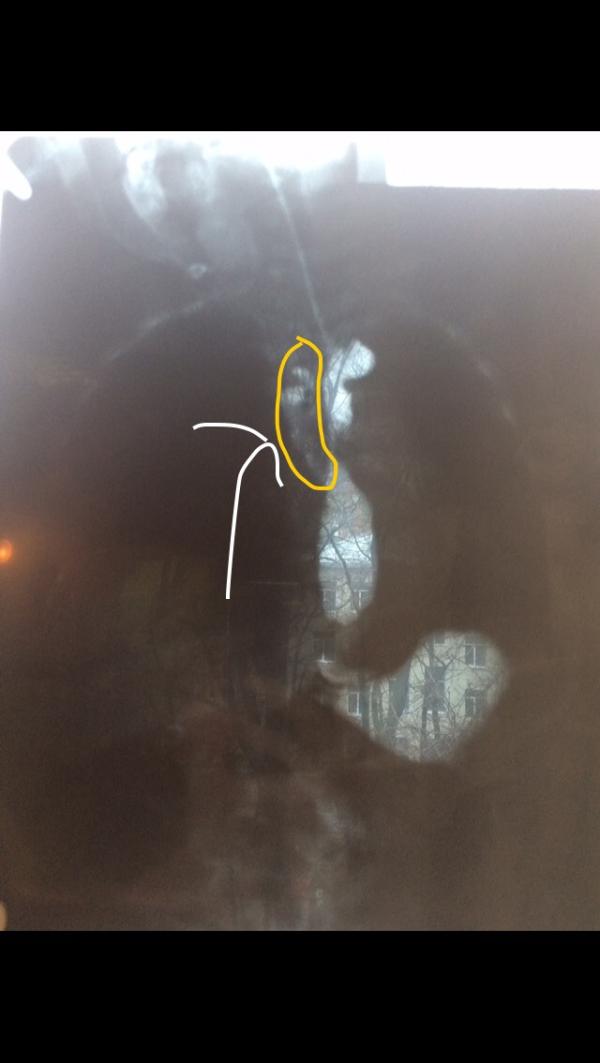

Но все-таки картина сложилась и в пн был тяжёлый разговор с профессором ... Он считает, что у нас редкий порок развития -удвоение пищевода ( это когда внутри одного пищевода ещё 2 ). И все это влияет на окружающие органы- трахею, бронхи, пищевод ... Это то, что мешало ему жить полноценной жизнью уже больше года ...